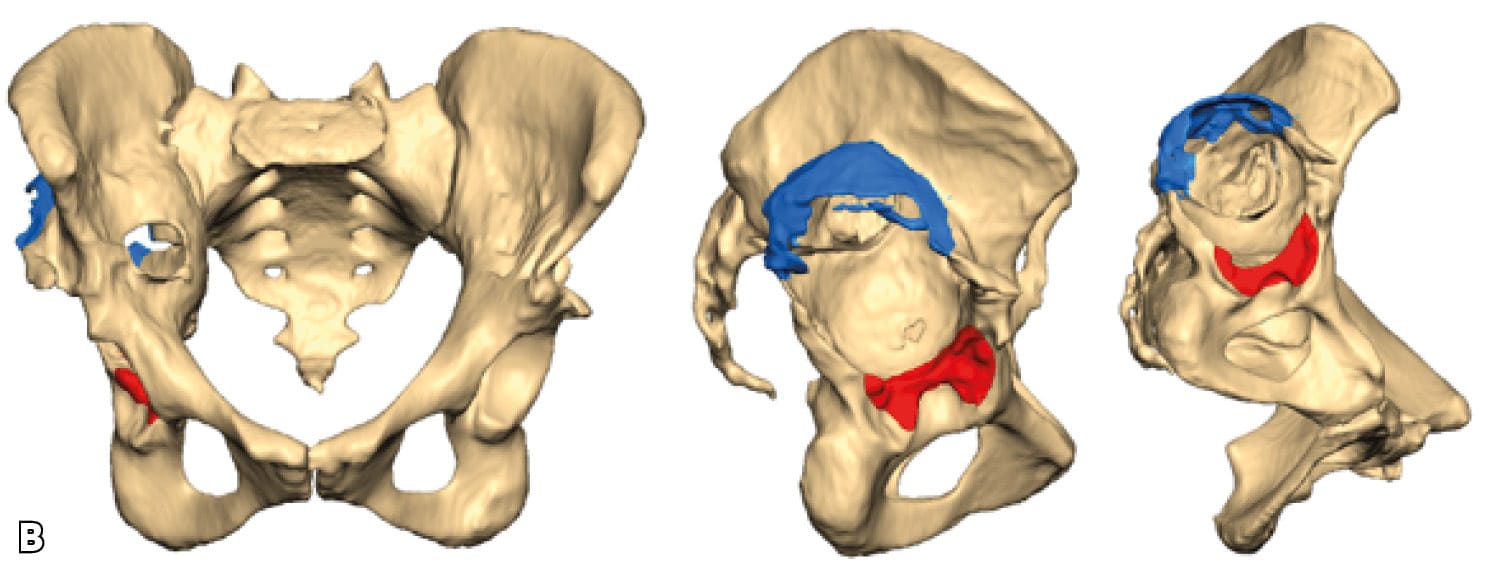

Severe post-operative defects. Principles of management and outcomes of specific patterns are not clearly reported in the literature. Based on the Sen clacification,[1] Sen RK, Mukhopadhyay R, Pattanshetti V, Saini G, Tripathy SK, Sethy SS, Sharma SK. A New Classification System for Acetabular Bone Defect Evaluation in Posttraumatic Acetabular Nonunion and Malunion. Indian J Orthop. 2022 Jun 27;56(9):1601-1612 types 1, 2, 3-A and 5 can be treated with surgical techniques used in revision THA surgery. For severe defects (such as 3-B, 4-A and 4-B), the restoration of hip center of rotation, cup offset, inclination and anterversion and hip stability can be achived only with custom-made implants (Figures 3 and 4).

Triflange and tumour like custom made acetabular impants. Modern technology allows the production of personalised implants for special conditions. These type of implants are custom made, porous coated titanium implants and are considered the last therapeutic salvage option, before excisional arthroplasty, for severe acetabular defects and PD. The implants are designed and manufactured based on pelvic models created by thin-slice pelvic 3-D CT-scans with metal subtraction software (Figures 7 and 8). Early and mid-term outcomes are encouraging but premium cost and length of production time limit their use.[20], DeBoer DK, Christie MJ, Brinson MF, Morrison JC. Revision total hip arthroplasty for pelvic discontinuity. J Bone Joint Surg Am. 2007; 89(4):870-876.[21], Taunton MJ, Ferhing TK, Edwards P, Bersasek T, Holt GE, Christie MJ. Pelvic discontinuity treated with custom triflange component: a reliable option. Clin Orthop Relat res. 2012; 470(2):428-434.[22] Zhang Y, Gao Z, Zhang B, Du Y, Ma H, Tang Y, Liu Y, Zhou Y. The application of custom-made 3D-printed titanium augments designed through surgical simulation for severe bone defects in complex revision total hip arthroplasty. J Orthop Traumatol. 2022; 6:23(1):37.